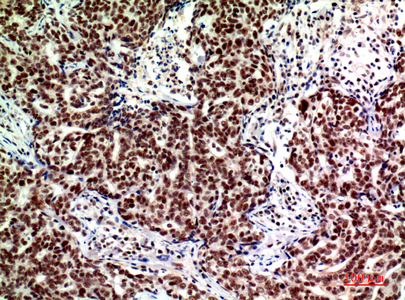

- Immunohistochemistry analysis of paraffin-embedded Human breastcancer using ASAH3L antibody. High-pressure and temperature Sodium Citrate pH 6.0 was used for antigen retrieval.